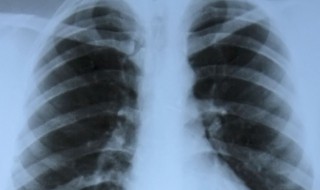

1、肺部小结节一般是在体检的时候发现,肺部CT显示肺部类圆形病灶,肺部小结节的种类,分为孤立性结节和多发性结节,肺部结节有的可以自行消失,有的不会消失,局部病灶直径大于3cm者称为肺肿瘤。

2、肺部小结节并不等于早期肺癌,肺内很多疾病都会形成结节,良性的如炎症、结核、霉菌、亚段肺不张、出血、等。因此肺内的小结节性病灶,可能的诊断可以说是多种多样,良性的包括炎性假瘤、错构瘤、结核球、真菌感染、硬化性肺细胞瘤等。恶性的则可能是原发性肺癌或肺内转移癌。当然部分良性病变,长时间之后也可能转化为恶性。据人群大样本的统计表明,直径大于25px(1cm=25px)的肺内单发小结节,恶性的占到一半以上。这样的数据告诉我们,决不可轻视体检时无意发现的肺内小结节。初次CT检查发现的肺部小结节,80%-90%都是良性病变,但却要高度重视,因为仍有一定比例的早期肺癌,定期检查必不可少。